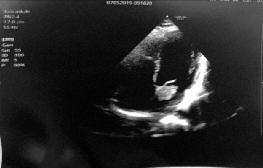

261 Riscontro ecocardiografico di mixoma atriale durante la valutazione dell’idoneità cardiologica ai fini del reclutamento in Forza Armata

E ch o c a r d i o g r a p h i c e v i d e n c e o f a t r i a l m y x o m a d u r i n g t h e assessment of cardiological suitability for recruitment into the Armed Force

Le visite di idoneità concorsuale, al pari di quelle arruolative all’epoca della leva, possono fungere da screening della popolazione giovane Il riscontro di anomalie congenite o acquisite, spesso misconosciute, può evitare conseguenze sanitarie gravi per il candidato, particolarmente in campo cardiologico